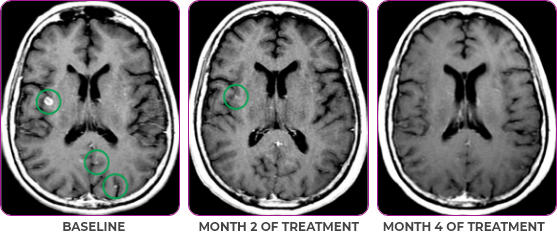

Response in primary and metastatic lesions1

MRIa imagery of the brain. Green circles indicate baseline brain metastases.1

SCAN 2: BRAIN

aMRI, magnetic resonance imaging.

Response to VITRAKVI1,2

- Partial response to treatment that was confirmed at 2 months (34% tumor reduction)

- Patient remains on VITRAKVI after more than 4 months of treatment